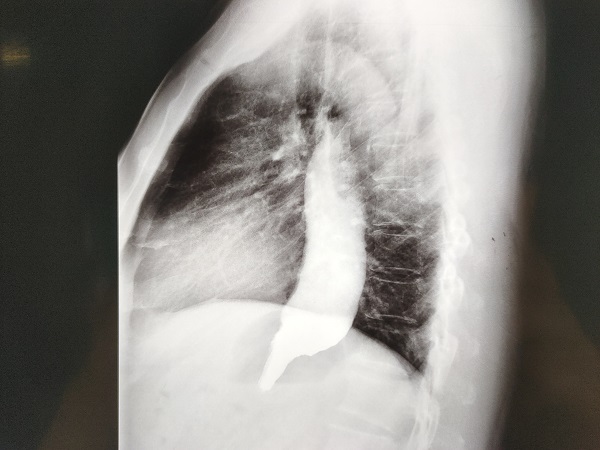

近期,孕30⁺²周、出生仅1.75kg的早产儿在宜春学院第一附属医院万载县人民医院新生儿科团队18天的全力救治和精心呵护下,转危为安,顺利出院。时间回到9月底,宜春学院第一附属医院万载县人民医院五病区安静的病房被一阵急促的电话声打破:“早产儿30⁺²周,胎盘早剥、足先露、产前有胎心下降,提示有宫内窘迫,胎儿情况危急,急需新生儿科医生紧急会诊”。接到通知后,新生儿医生立马赶到产房,与妇产科医生一起评估胎儿情况,考...